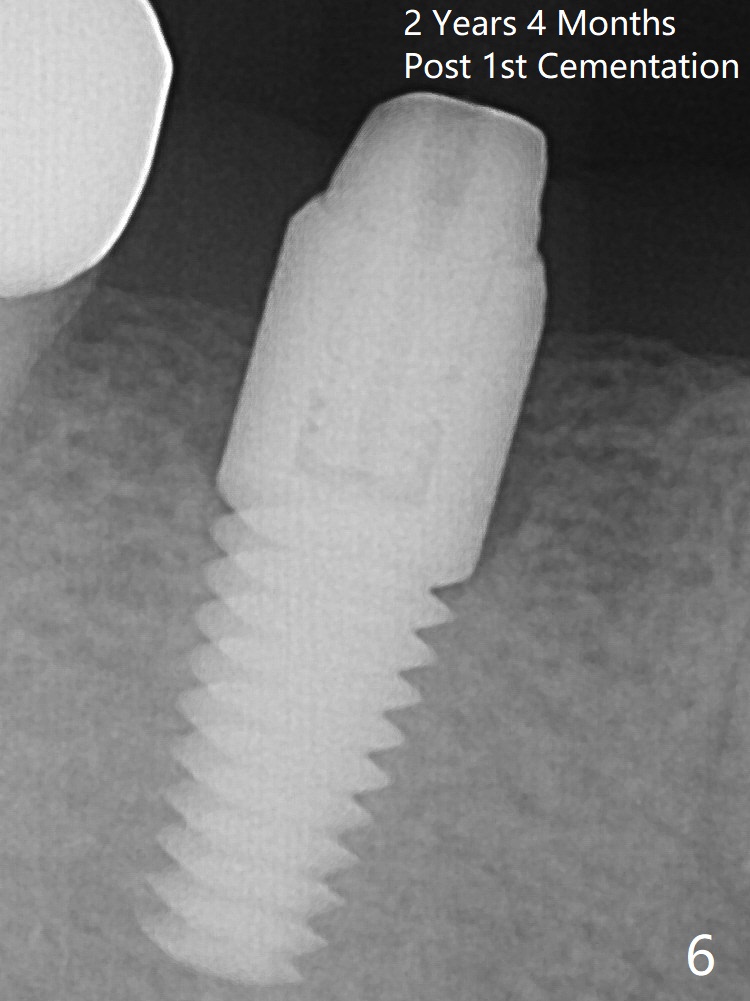

The crown over the implant has dislodged 3 times over 28 months post cementation (Fig.6).  It appears that the top of the abutment is too rounded.  Bone density seems to remain the same after cementation of a new crown (Fig.7).